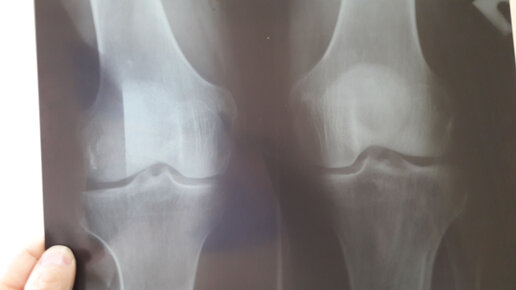

Лечение гонартроза коленного сустава 2 степени

Гонартроз: симптомы и лечение деформирующего артроза коленного сустава

Тупая ноющая боль в колене, скованность, хруст при движении, покраснение и припухлость кожи ― довольно типичные признаки гонартроза. Гонартроз является хроническим дегенеративным заболеванием, которое приводит к нарушению целостности хряща, прогрессирующий патологический процесс, постепенно охватывающий все элементы суставного сочленения, приводит к выраженному нарушению двигательной функции, снижает трудоспособность и даже становится причиной инвалидности. Разбираемся в причинах заболевания, симптомах, методах диагностики и лечения...